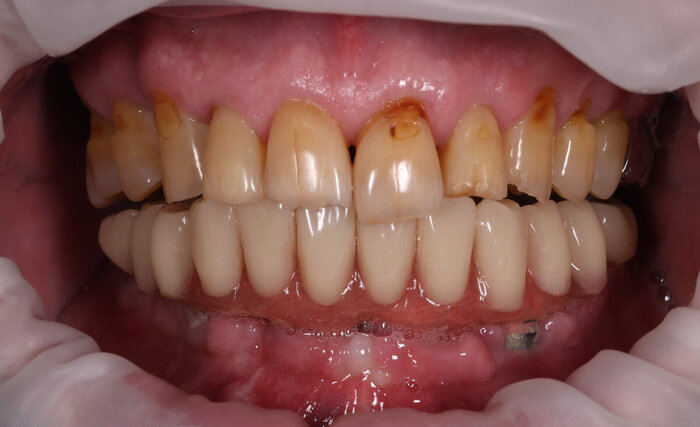

Посмотрим, что во рту:

Временный адаптационный протез с опорой на 6 имплантов. Нижняя челюсть.

До.

До имплантации.

А вот что стало после.